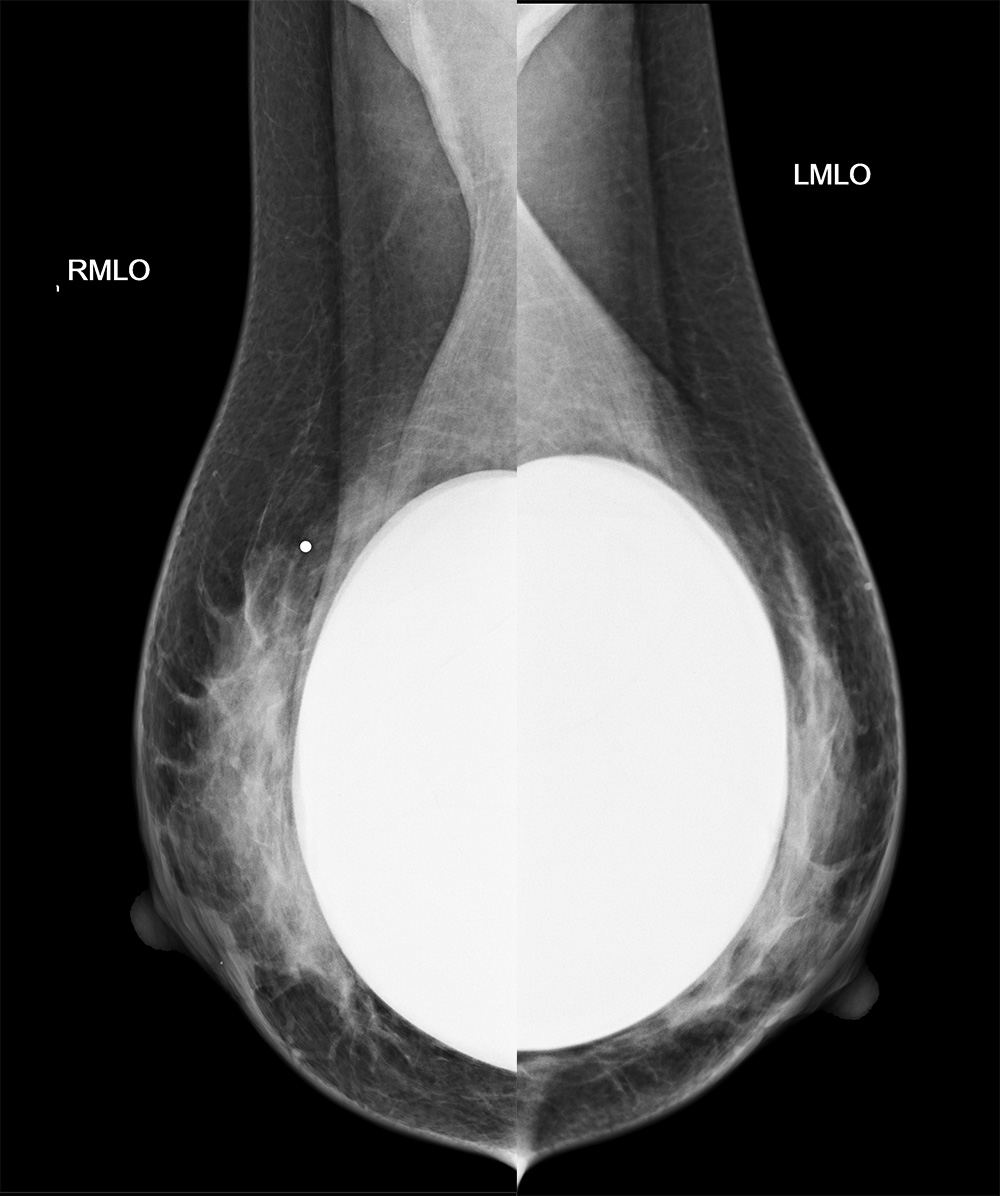

◂Breast Anatomy